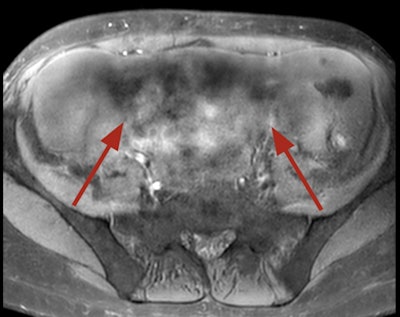

Dielectric effect, or standing wave effect, artifacts may be seen in cases of profuse ascites or in obese and pregnant patients, and it is due to the high magnetic field in a 3-tesla machine that can't maintain its homogeneity. Bright or dark "holes" in regions away from the receive coil caused by interference with the standing waves. These artifacts become more pronounced the larger the region of interest.

Dielectric artifact. Axial echo gradient fat-saturated T1-weighted slice of the abdomen acquired on a 3-tesla device, showing multiple blurred areas of signal loss (arrows) at distance of the receiving coil, in a patient with abundant ascites. The strategy in this case would be first to apply parallel radiofrequency transmission technique, and if insufficient, to rescan the patient on a 1.5-tesla scanner."Pregnant patients should always be explored at 1.5T," the authors pointed out. "Ascites can be handled by switching to a lower magnetic field device or drained before the exam. Parallel radiofrequency (RF) transmission or any other technology improving RF emission homogeneity will reduce dielectric effects (e.g., Philips' MultiTransmit, Siemens' TimTx, GE's MultiDrive, Canon's Multiphase Transmit).